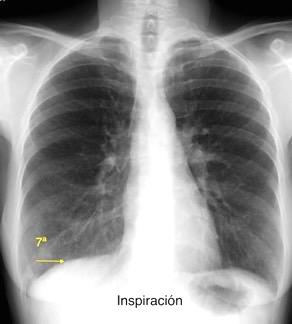

Excursión diafragmática: 0,8-8cm Derecho mas alto (2-3 cm) 89% (Felson)

Nason LK. Imaging of the diaphragm: anatomy and function. Radiographics 2012

El diafragma tiende a estar más plano:

1º. Con la vejez, 2º. Con mayor peso.

3º. Con dimensiones torácicas anchas Suwatanapongched. Chest 2003